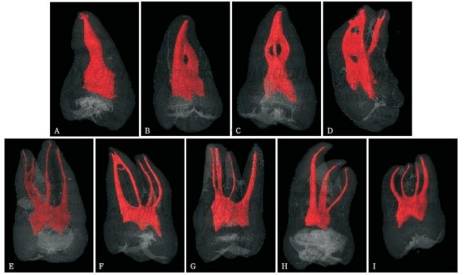

複雜的根管係統